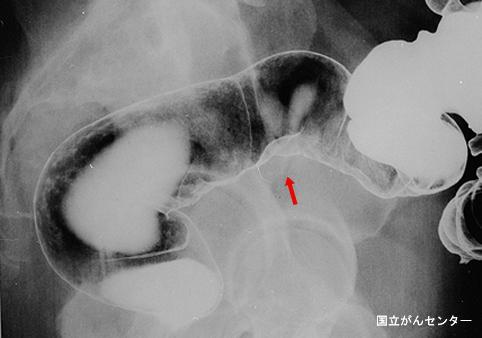

疾病(病理主体)的分类其他肿瘤/恶性阑尾粘液肿瘤

部位(按器官分)大肠/乙状结肠

检查方法X线

肿瘤最大直径25~29